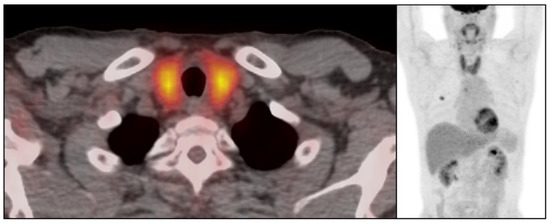

3.2. Immune-Related Thyroiditis Based on Imaging Findings

3.5. Temporal Changes in the CT Findings Correlating with TSH